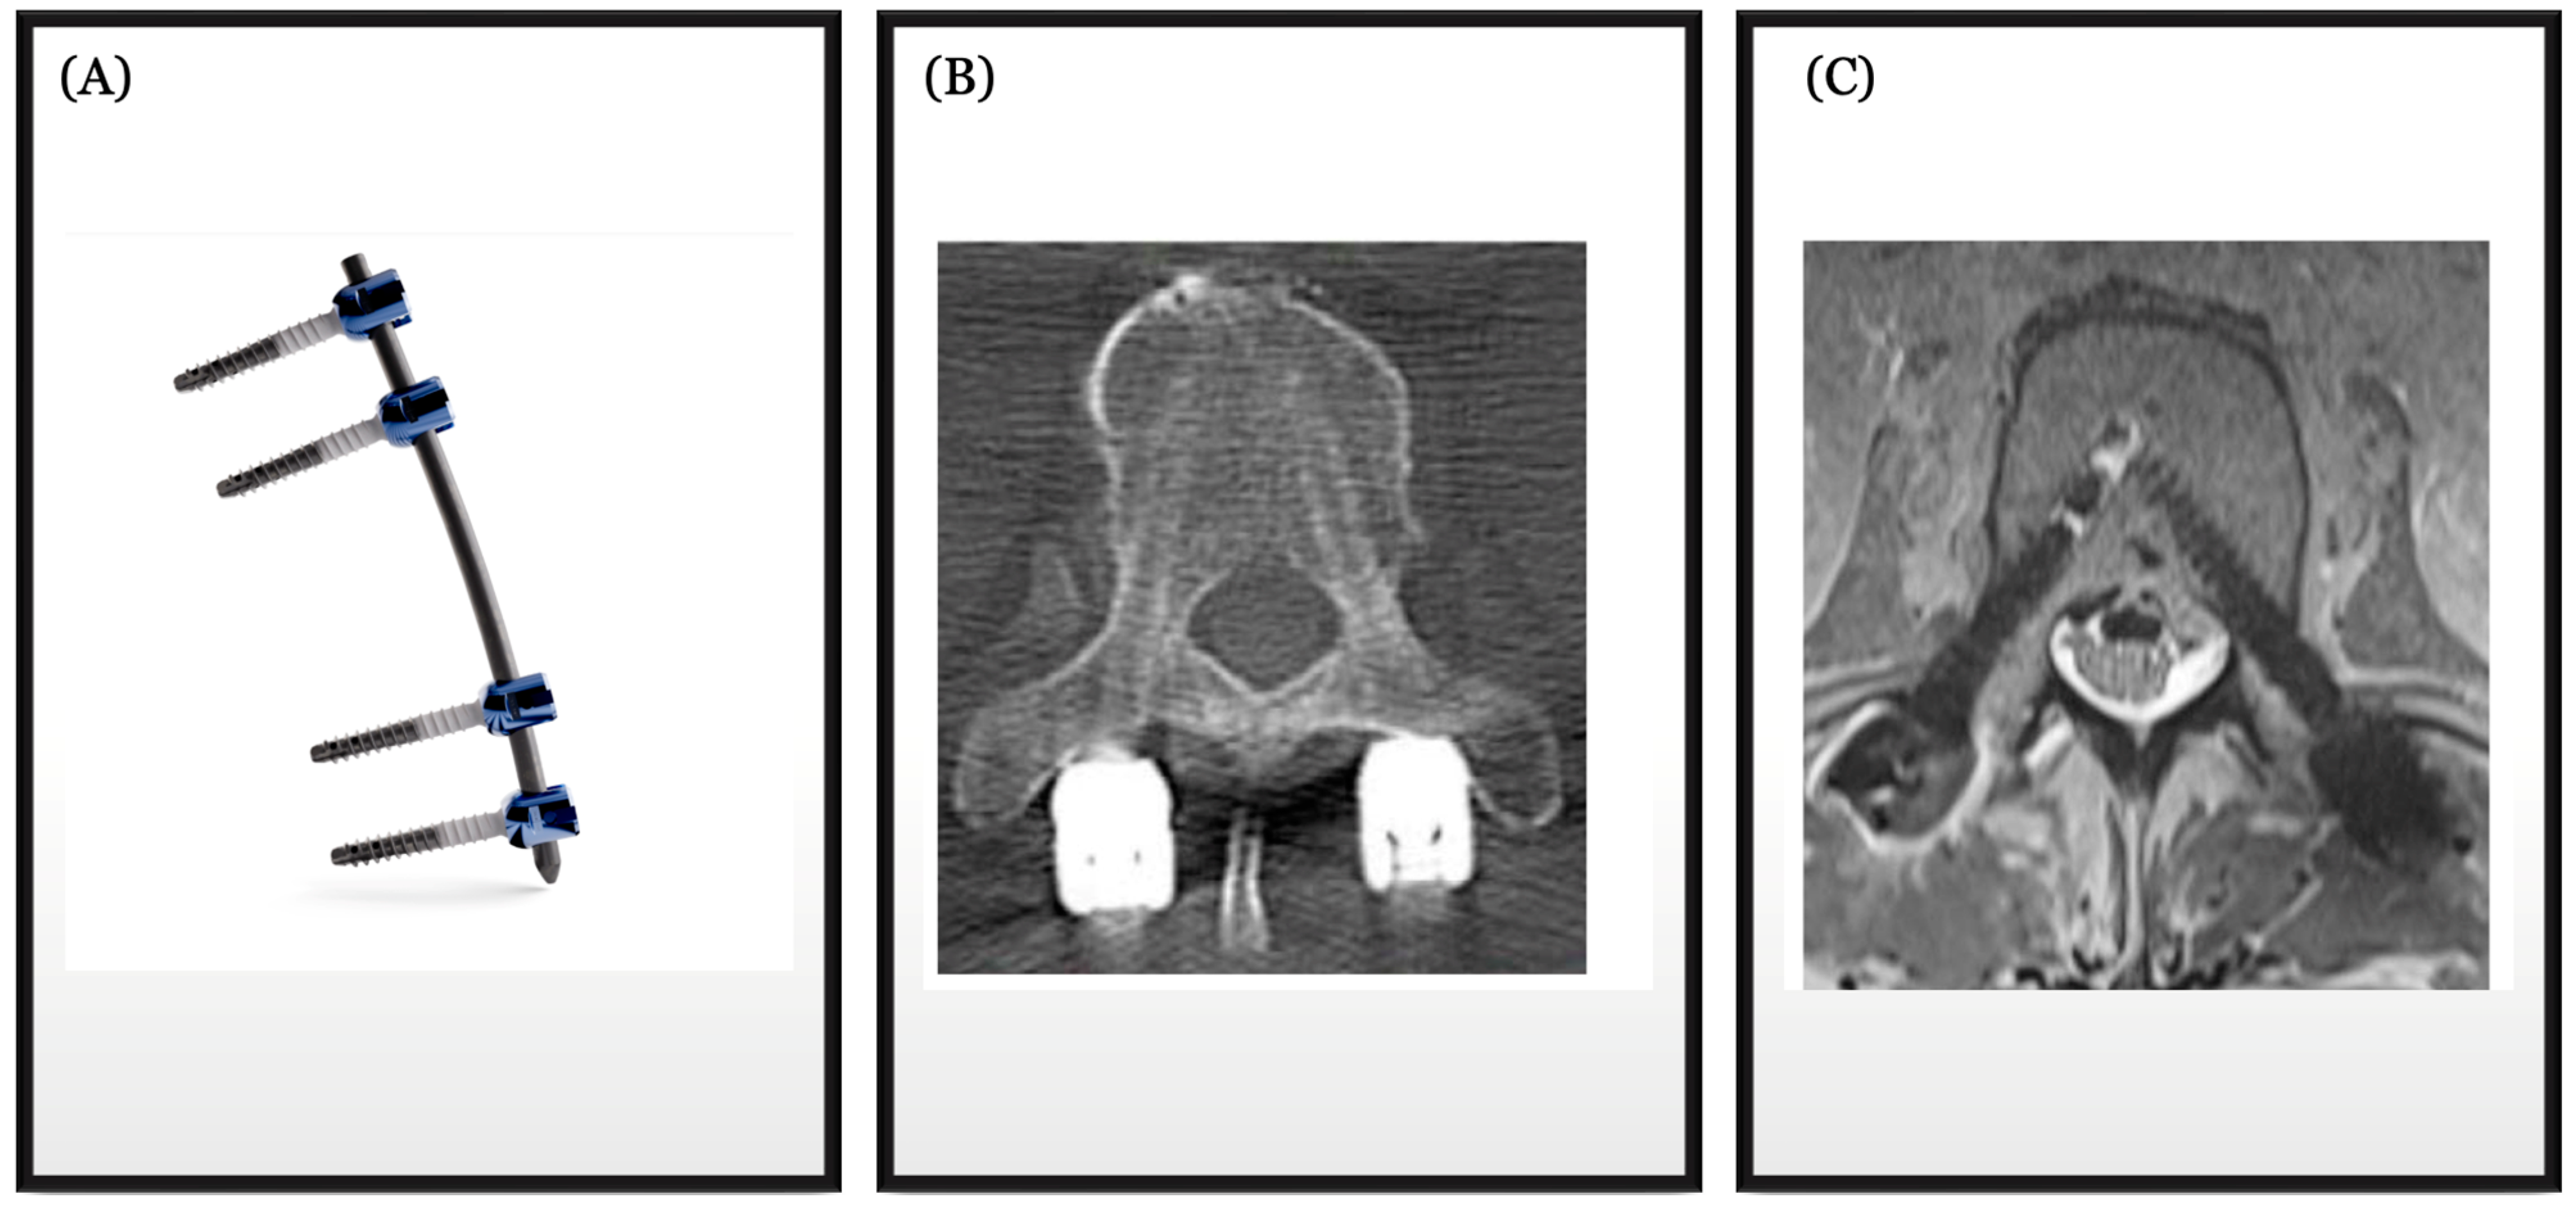

- Uri, O.; Folman, Y.; Laufer, G.; Behrbalk, E. A Novel Spine Fixation System Made Entirely of Carbon-Fiber-Reinforced PEEK Composite: An In Vitro Mechanical Evaluation. Adv. Orthop. 2020, 2020, 4796136. [Google Scholar] [CrossRef] [PubMed] [PubMed Central]

- Krätzig, T.; Mende, K.C.; Mohme, M.; Kniep, H.; Dreimann, M.; Stangenberg, M.; Westphal, M.; Gauer, T.; Eicker, S.O. Carbon fiber-reinforced PEEK versus titanium implants: An in vitro comparison of susceptibility artifacts in CT and MR imaging. Neurosurg. Rev. 2021, 44, 2163–2170. [Google Scholar] [CrossRef] [PubMed] [PubMed Central]

- Murthy, N.K.; Wolinsky, J.P. Utility of carbon fiber instrumentation in spinal oncology. Heliyon 2021, 7, e07766. [Google Scholar] [CrossRef] [PubMed] [PubMed Central]

- Schwendner, M.; Ille, S.; Kirschke, J.S.; Bernhardt, D.; Combs, S.E.; Meyer, B.; Krieg, S.M. Clinical evaluation of vertebral body replacement of carbon fiber-reinforced polyetheretherketone in patients with tumor manifestation of the thoracic and lumbar spine. Acta Neurochir. 2023, 165, 897–904. [Google Scholar] [CrossRef] [PubMed] [PubMed Central]